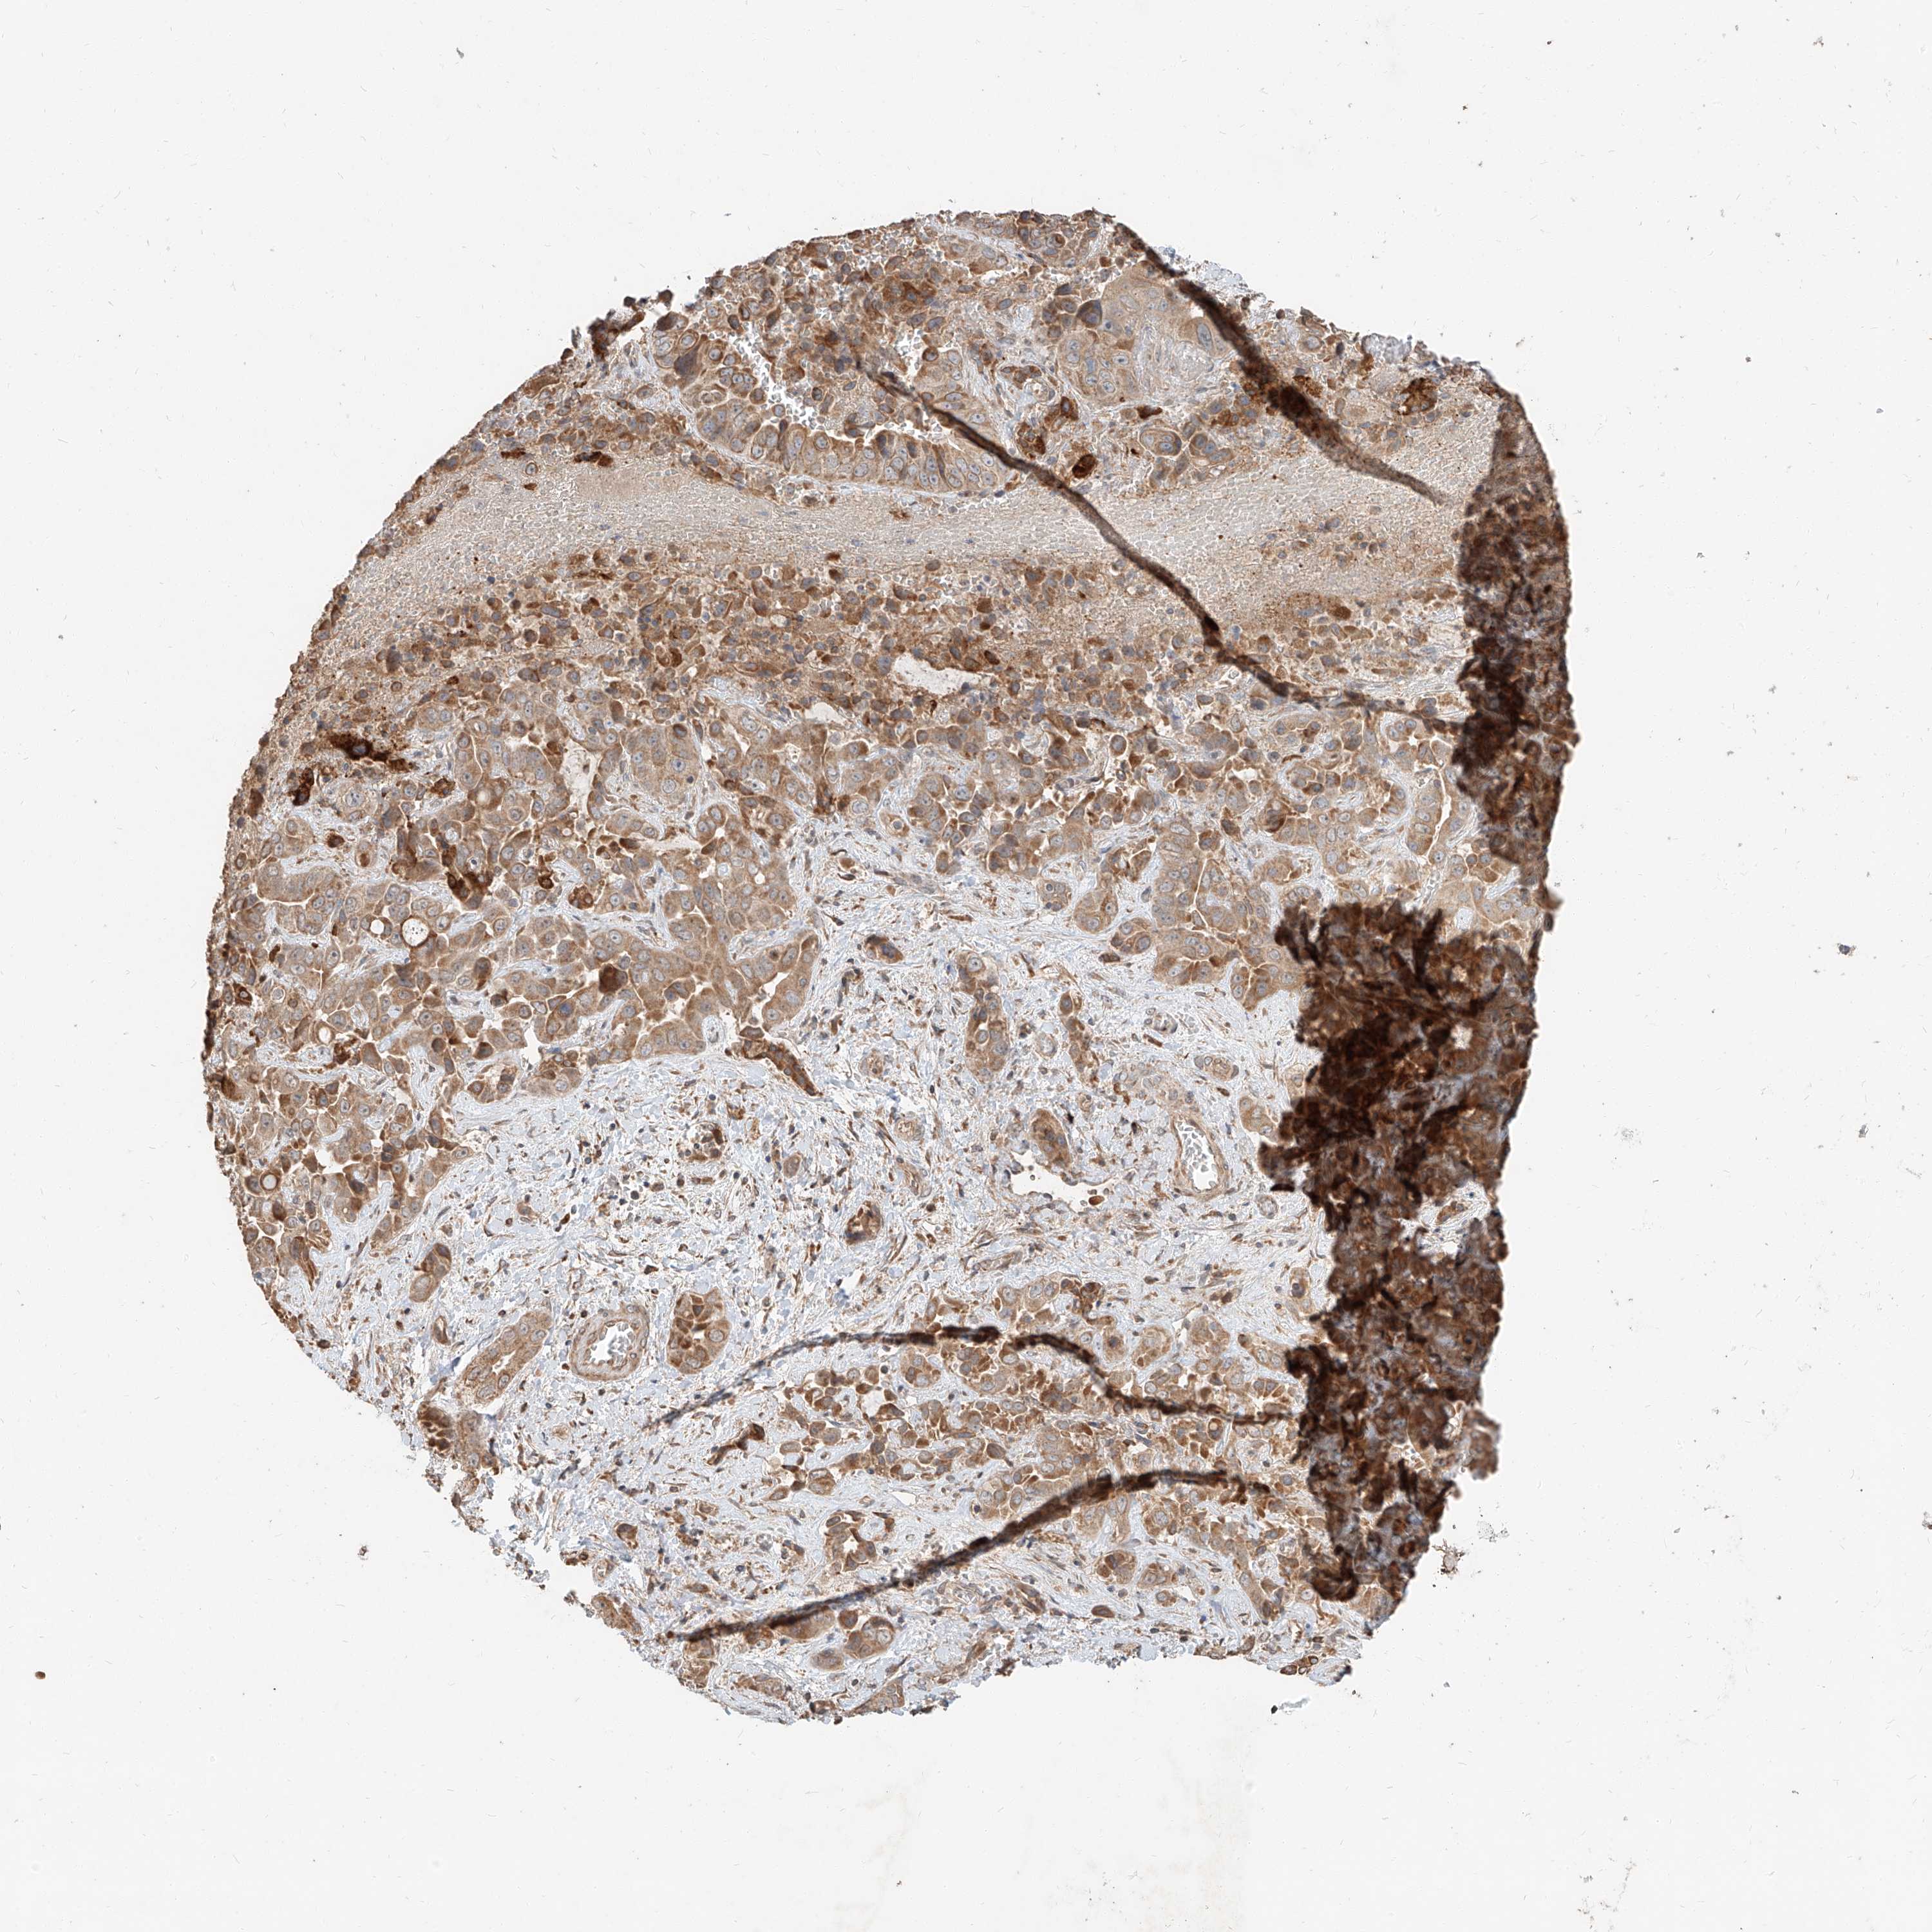

LIVER CANCER - Protein expressioni

A mouse-over function shows sample information and annotation data. Click on an image to view it in a full screen mode. Samples can be filtered based on level of antibody staining by selecting one or several of the following categories: high, medium, low and not detected. The assay and annotation is described here.

Note that samples used for immunohistochemistry by the Human Protein Atlas do not correspond to samples in the TCGA dataset.

Antibody stainingi

Antibody staining in the annotated cell types in the current human tissue is reported as not detected, low, medium, or high, based on conventional immunohistochemistry profiling in selected tissues. This score is based on the combination of the staining intensity and fraction of stained cells.

Each image is clickable and will lead to virtual microscopy that enables deeper exploration of all samples and also displays staining intensity scores, fraction scores and subcellular localization as well as patient and tissue information for each sample.

Antibody HPA030604

Staining

High

Medium

Low

Not detected

Intensity

Strong

Moderate

Weak

Negative

Quantity

>75%

75%-25%

<25%

None

Location

Nuclear

Cytoplasmic/membranous

Cytoplasmic/membranous,nuclear

Cholangiocarcinoma

Carcinoma, Hepatocellular, NOS